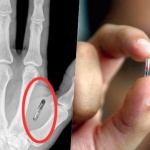

Американска компания ще вгражда чипове в служителите си

24 Юли 2017 | 20:56 /КРОСС/ Американска компания от щата Уисконсин направи реалност сценариите от бъдещето, когато хората ще живеят с имплантирани микрочипове, за да бъдат по-функционални. ...